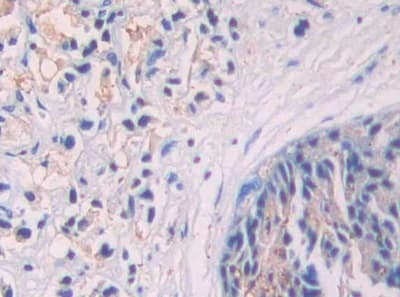

Rabbit Polyclonal SIGIRR antibody. Suitable for WB, IHC-P and reacts with Pig, Human samples. Cited in 1 publication. Immunogen corresponding to Recombinant Fragment Protein within Human SIGIRR aa 1-150.

Applications IHC-P, WB

Species Reactivity Human, Pig